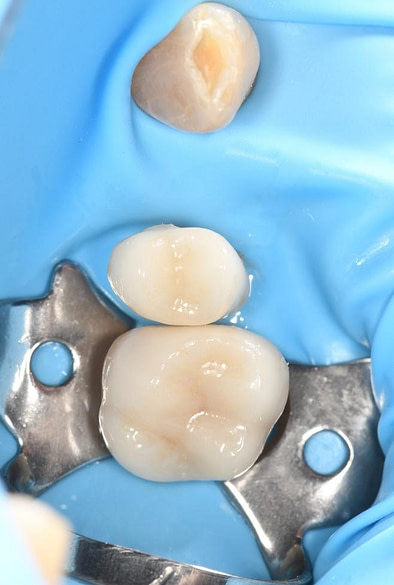

Digital impressions were captured using the TRIOS 4 intraoral scanner, and the implant-supported crown was designed using 3Shape Design Studio.

The crown was milled from a high-strength, multilayered zirconia and hand-finished to achieve a lifelike appearance.

At the final appointment, the crown was securely attached to the implant, resulting in a beautiful, natural-looking restoration.